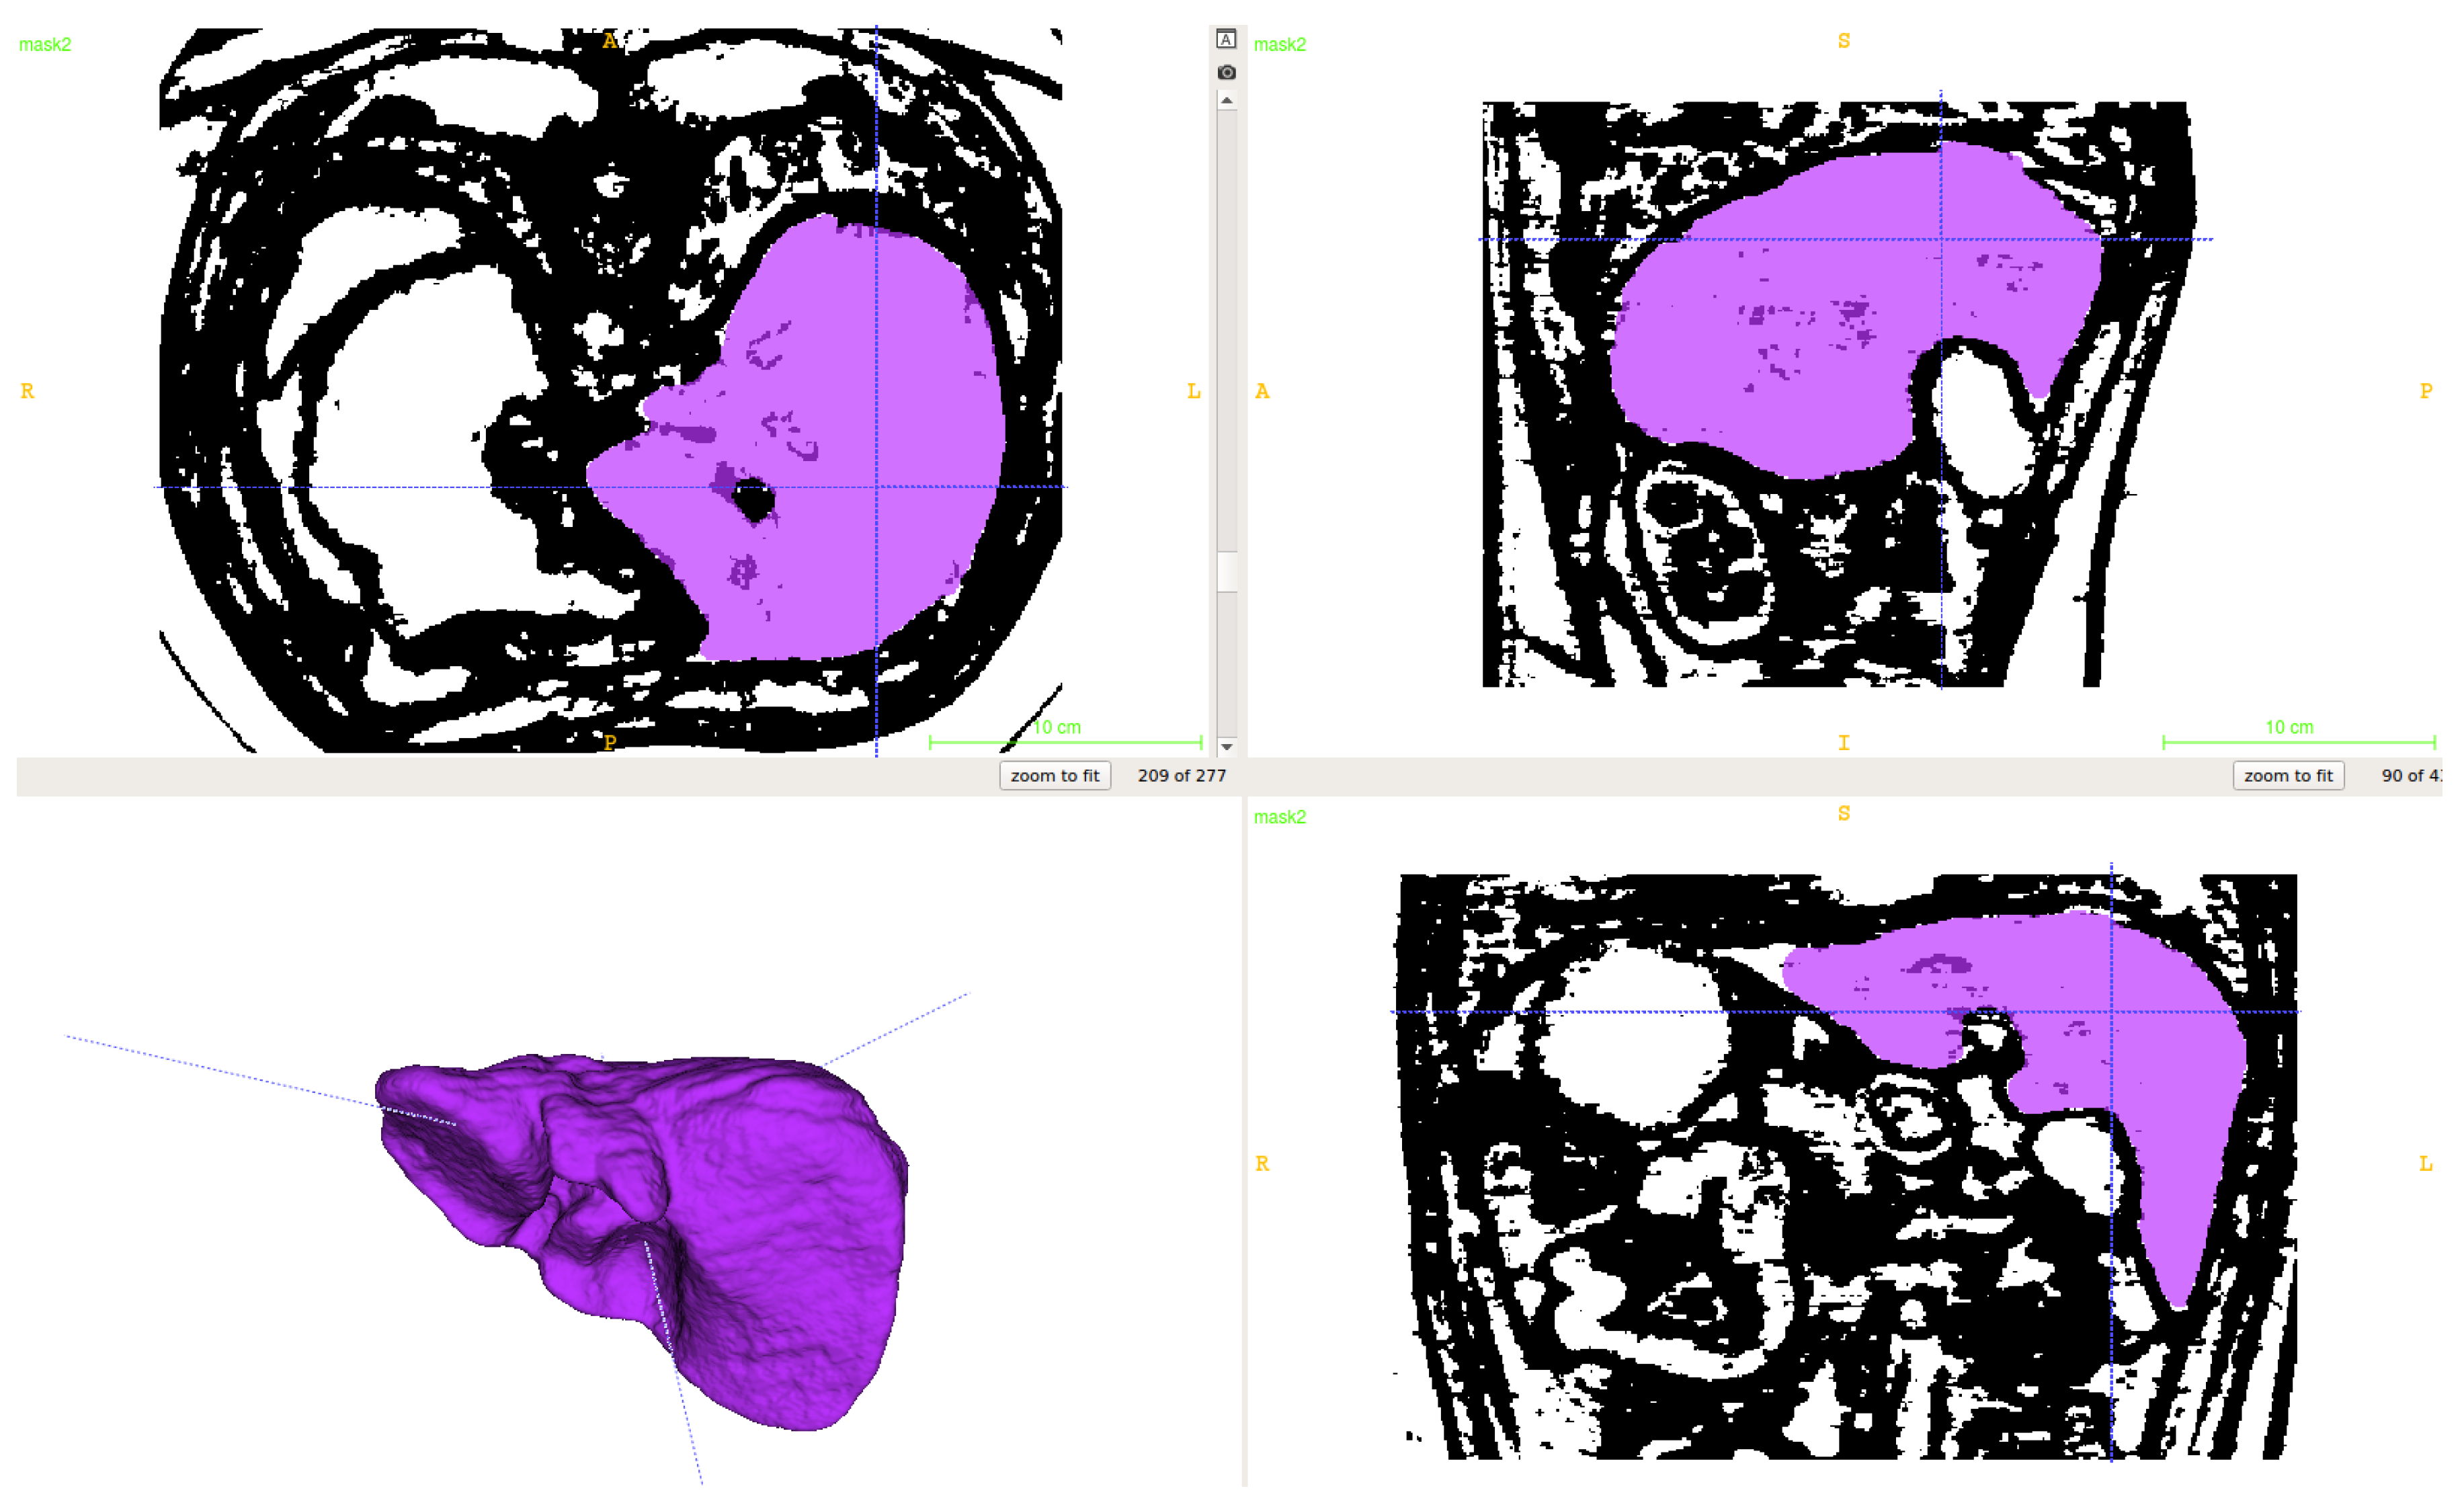

2.1. Segmentation of Abdominal Parenchymal Organs

- Pre-process and smooth the input dataset.

- Compute the spatial-dependence matrix (specified in [18]) for all voxels of the smoothed dataset.

- Compute entropy (1) for each voxel using the spatial-dependence matrix.

- Obtain the binary mask by entropy values thresholding.

- Set the seed points for organs extraction.

- Implement active contours method and extract 3D model.